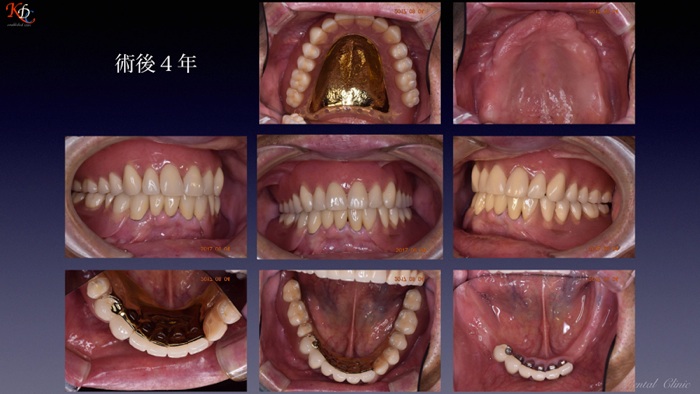

咬合再建・咬合回復shapeimage_22_link_0

症例に応じた治療手法の選択と咀嚼機能再現の効果http://www.kura-dent.com/Treatment%20and%20effects.pdfshapeimage_23_link_0